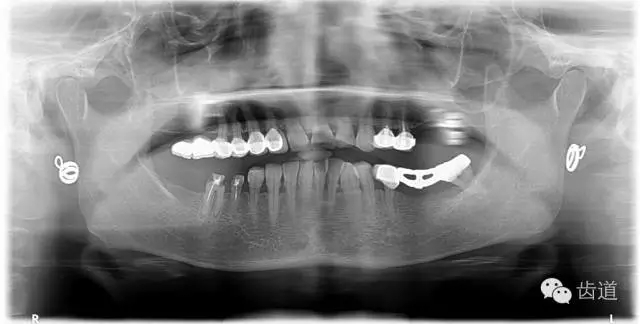

1、術(shù)前全景片

4、 全景片